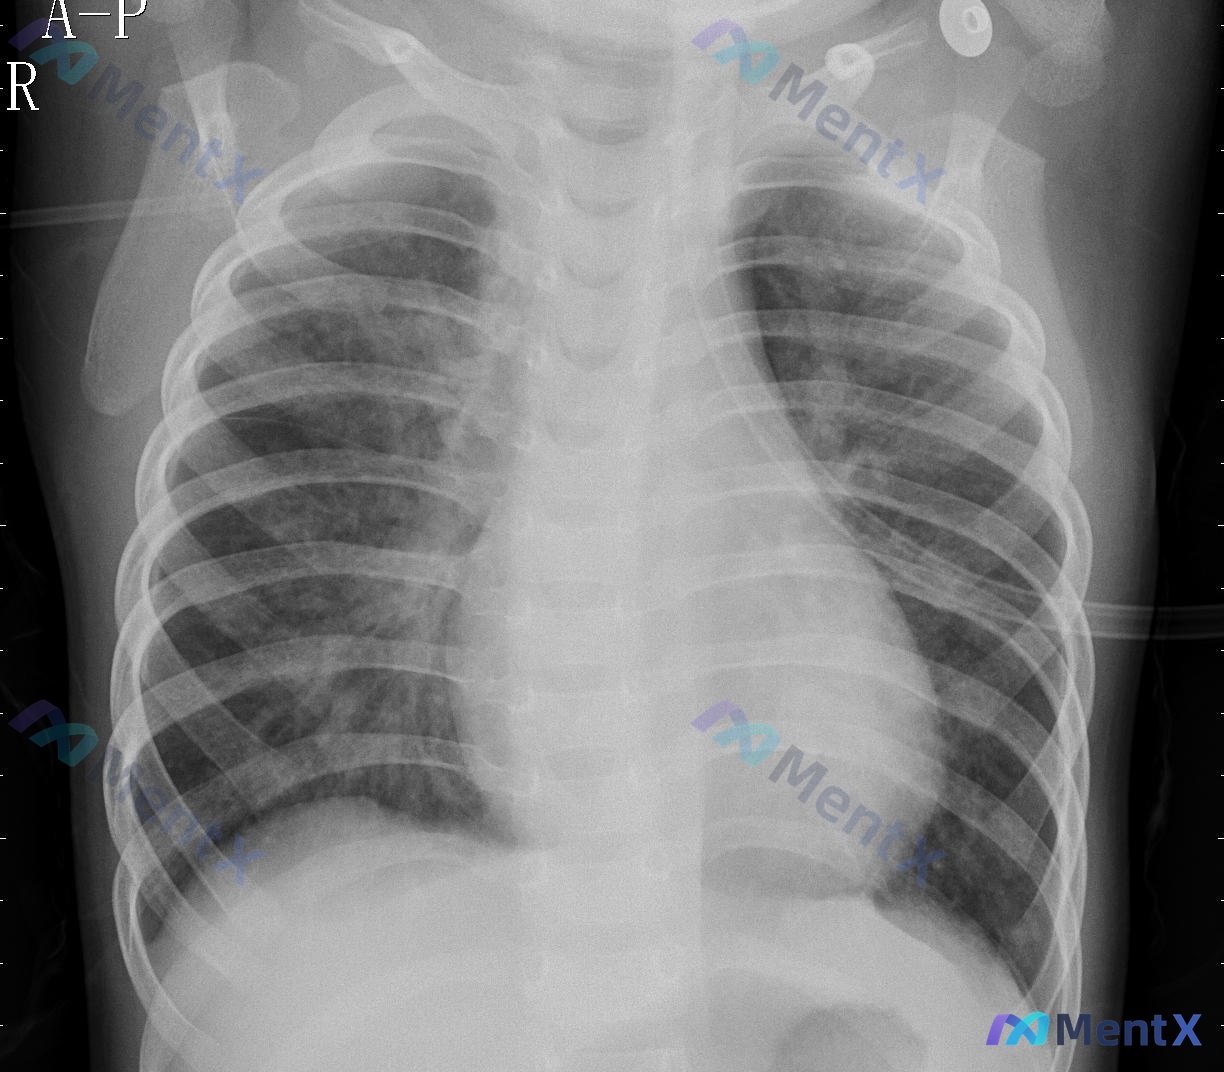

整理了一份儿童胸部X光片的分析资料,先不说结论,大家先看看前期表现的思路会不会分叉? 基础情况:儿童,胸部正位/前后位(A-P,床旁摄片常见)。 影像关键表现: - 气管纵隔居中,双侧肺野透亮度对称,无明显实变/空洞/肿块; - 双侧肺纹理较丰富,主要集中在肺门周围及内中带; - 心影比例看起来较大...

整理到一张婴幼儿的胸部正位片(仰卧位AP位),影像描述有点意思: 核心异常: - 双肺纹理明显增粗、增多,伴模糊斑片状影,以双肺内中带及肺门周围为主 - 双肺门影似乎略有增大、结构模糊 - 肺野透亮度略有下降 关键阴性: - 气管居中、纵隔心影正常(符合婴幼儿生理) - 无明确实变、无积液、无气胸...